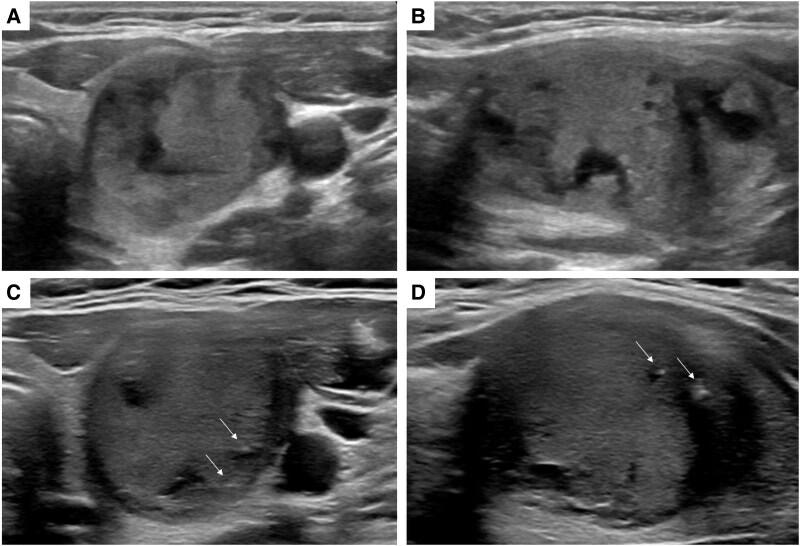

Cribriform morular thyroid carcinoma (CMTC) is a rare thyroid malignancy strongly associated with familial adenomatous polyposis (FAP). About 50% of CMTC cases are associated with FAP, including a subset in which CMTC is the presenting symptom in previously undiagnosed FAP. We present a case of a young woman with thyroid nodules monitored for several years due to low suspicion ultrasound features. After development of macrocalcifications in 1 nodule, she had a fine needle aspiration (FNA). The cytology was concerning for papillary thyroid carcinoma. She underwent total thyroidectomy with final pathology of CMTC. Given the strong association between CMTC and FAP, the patient completed endoscopy, colonoscopy, and genetic testing, which led to a diagnosis of FAP. The diagnosis of CMTC can be difficult because nodules are often small without concerning ultrasound features, not meeting recommendations for FNA. Due to an increased risk of CMTC in individuals with FAP, current criteria may be inadequate in identifying nodules warranting thyroid FNA. Continued ultrasound surveillance should be considered for nodules with low suspicion ultrasound features in this population.